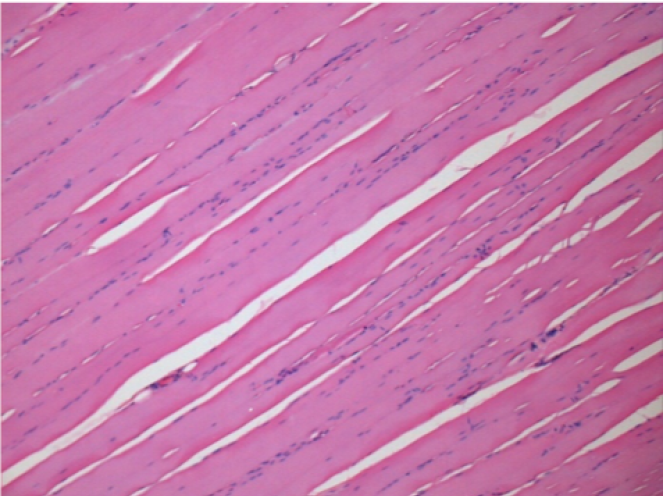

3 mesi dopo Iniezione di Endopeel

Scatola Nr 4

3 mesi (Giorno90) dopo iniezione 0.1ml di Endopeel nel muscolo pretibiale destro ( Dx)

Sx : Controllo-100x-Giorno90

Dx:100x-Giorno90